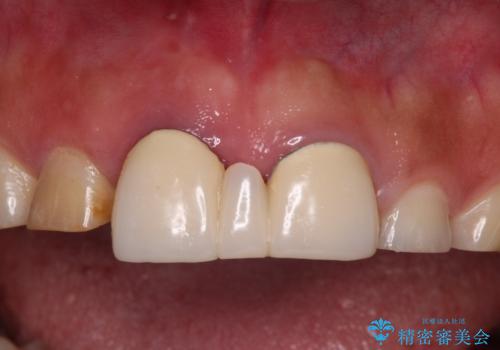

不自然な前歯 歯肉移植を用いた前歯のオールセラミックブリッジ

- 前歯の違和感と不自然な形態のブリッジを気にして来院された患者様です。

検査したところ、右前歯は抜歯が必要であったので、ブリッジを新製することとしました。

抜歯をすると歯肉が窪んでしまうので、傷口の治りを待って、歯肉移植を行うこととしました。

歯肉移植や根管治療終了後、オールセラミッククラウンおよびブリッジにて補綴することとしました。

歯の幅径のバランスが取れ、自然な口元となりました。